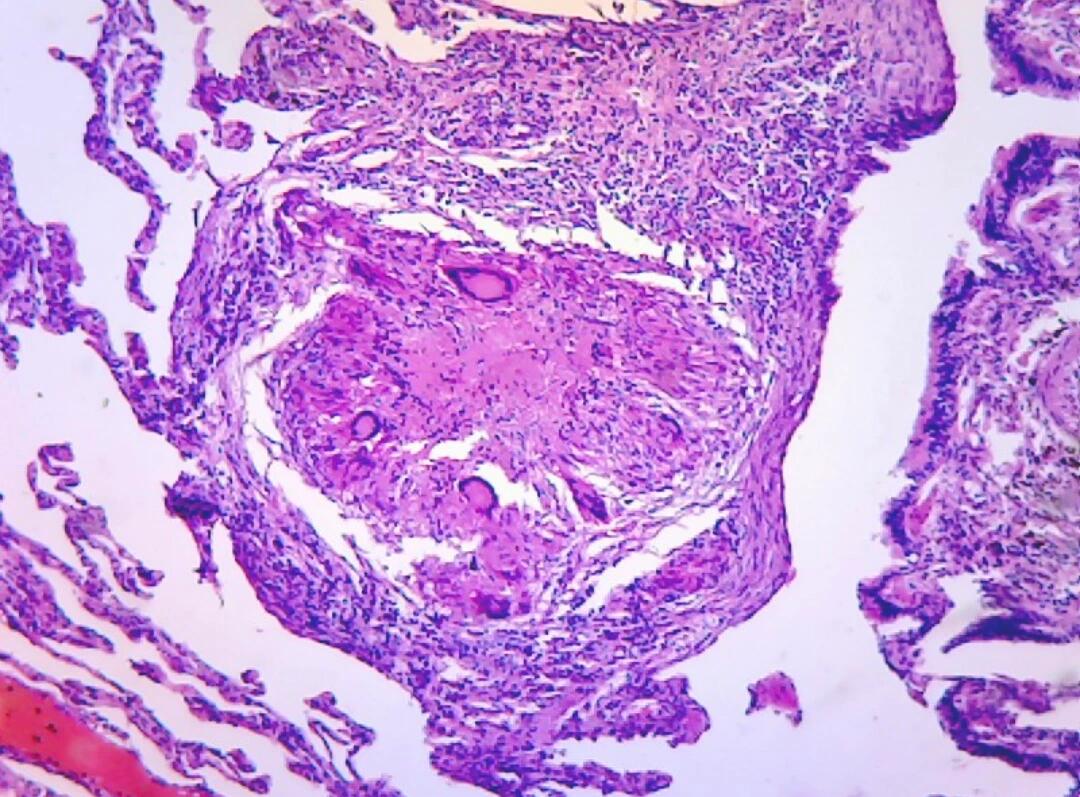

病理组织观察

肺结节穿刺活检病理:肺结核.#肺结节 #肺穿刺活检 #手术室